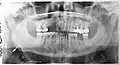

Панорамная рентгенограмма, показывающая дефект Стафне (отмечен стрелкой)